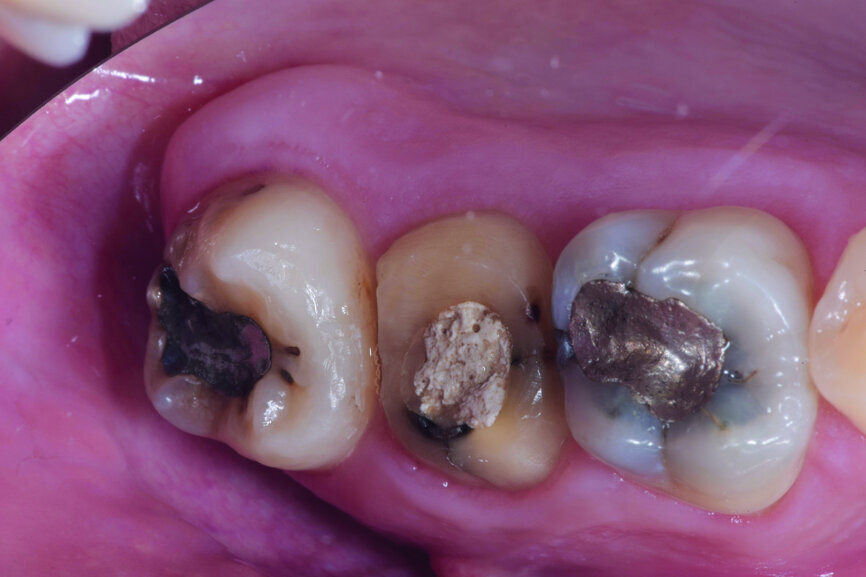

Fig. 1: Pre-op occlusal view.

Fig. 2: Pre-op facial view.

A 47-year-old male patient in a good medical condition and a non-smoker was referred to our dental practice for endodontic retreatment of the right maxillary second molar. The dental history revealed that the tooth had been endodontically treated three months before because of acute pulpitis. After the treatment, the patient complained of pain on chewing. Antibiotics and a non-steroidal anti-inflammatory drug were prescribed, but the pain remained. After a month, a sinus tract appeared. The tooth was retreated in another practice without success. The clinical inspection revealed the presence of a sinus tract near the apical region of tooth #17. The tooth had been prepared for a full crown, but was without even a temporary crown, and the access cavity had been closed with temporary filling material. Cracks were evident on the buccal and mesial surfaces. Periodontal probing showed a deep pocket (> 12 mm) on the distal aspect of the root trunk (Figs. 1 & 2). The periapical radiograph showed a radiolucency between the roots of the second and third molars. The radiographic appearance of the endodontic treatment was good, without clear evidence of periapical radiolucencies (Fig. 3). A perforation of the pulp chamber floor was suspected. A CBCT scan was performed (Figs. 4–7), and it confirmed the suspicion of perforation, along with the presence of a large periradicular radiolucency and an unfavourable root shape.